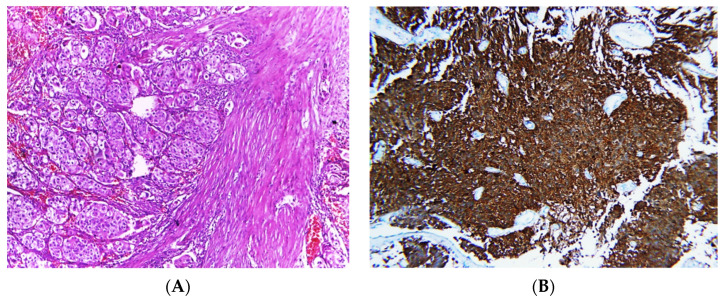

Invasive tumors were diagnosed according to specific microscopic criteria; neoplastic cells arranged in irregular nests or single cells invading the lamina propria and muscle layer (muscularis propria) (Figure 2).

Figure 2.

Photomicrographs of MIBC cases. Histopathological features of muscle-invasive urothelial carcinoma (A). Immunostaining for p16 in MIBC showing strong nuclear and cytoplasmic expression (B). Immunostaining for p53 in MIBC showing positive nuclear expression > 20% of cells (C). Immunostaining for Ki-67 in MIBC showing positive nuclear expression (D) (original magnification ×100).